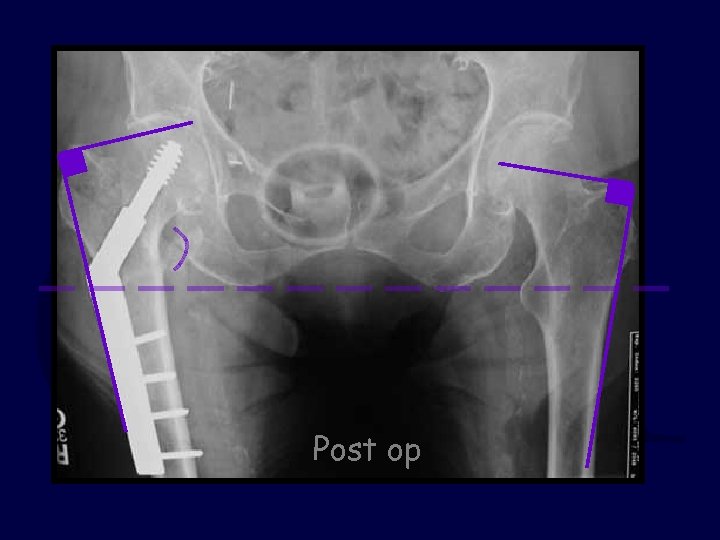

81 y. o. female slipped & fell 3 part IT fx Discuss: Did the surgeon do a good job? Yes or No Post-op X-rays

Post op

The TAD was acceptable but the reduction was grossly short